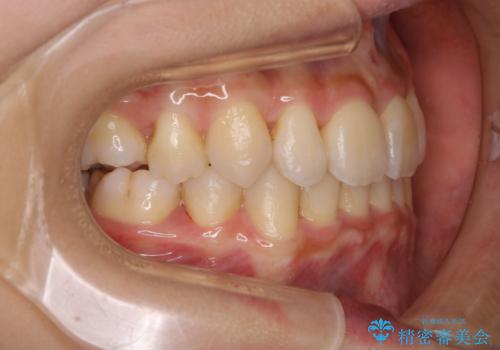

- 元々は海外でワイヤー矯正を行っていたが、コロナ禍で海外への往来が難しくなり、治療を中断せざるを得なくなってしまった方です。

ご本人のご希望により、インビザラインによる治療を行いました。

ブラケット除去直後に目立っていた下顎前歯部の大きなブラックトライアングルもあまり目立たなくなり、大変喜んでいただけました。